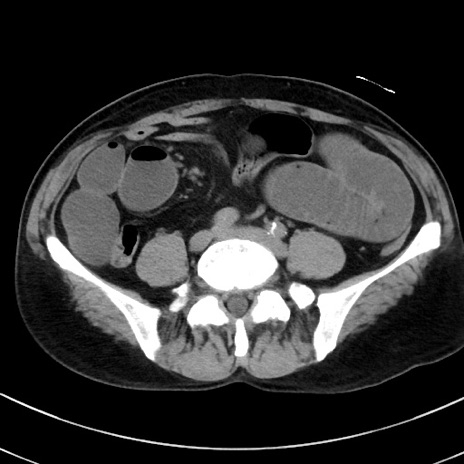

症例38(横断像)

【症例】70歳代 男性

【主訴】腹痛・嘔吐

【現病歴】昨晩より、嘔吐・腹痛あり。今朝になっても嘔吐あり。来院。

【既往歴】心臓バイパス手術、開腹胆摘、腸閉塞

【身体所見】BP 107/71mmHg、HR 116/min、腹部:平坦、軟、下腹部に軽度圧痛あり。反跳痛なし。

【データ】WBC 15100、CRP 0.32